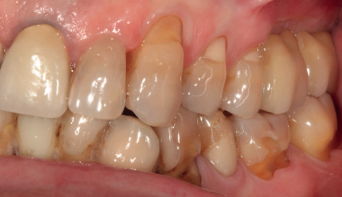

En la Figura 2 se muestran los diámetros y longitudes de los implantes incluidos en el estudio en función de los milímetros de cresta ósea residual en altura. La densitometría media de la zona de inserción del implante del grupo fue de 293,33 HU (+/- 144,99). El torque medio de los implantes estudiados fue de 27,33 Ncm (+/- 16,99). Todos los implantes se cargaron en dos fases quirúrgicas y en todos se llevó a cabo una elevación de seno transcrestal con injerto óseo autólogo particulado obtenido del fresado, embebido en PRGF-Endoret como marterial de injerto. En ninguno de los casos se registraron complicaciones relativas a la cirugía. Los implantes presentaron un seguimiento medio de 13,33 meses tras la carga (+/- 3,09), no encontrándose complicaciones ni fracasos durante este tiempo de seguimiento, por lo que la supervivencia fue del 100%. Todos los implantes fueron rehabilitados mediante prótesis múltiple atornillada mediante elemento intermedio (transepitelial múltiple, Multi-im®), encontrándose dos de los implantes ferulizados a otros de la misma longitud (4,5 mm) y el resto a longitudes mayores. La ratio corona-implante medio para el grupo de estudio fue de 2,43 mm (+/-0,45). La pérdida ósea mesial final media de todos los implantes fue de 0,42 mm (+/- 0,51) y la pérdida ósea distal final media de 0,16 mm (+/-0,34). En las Figuras 3 –13 se muestra uno de los casos incluidos en el estudio.